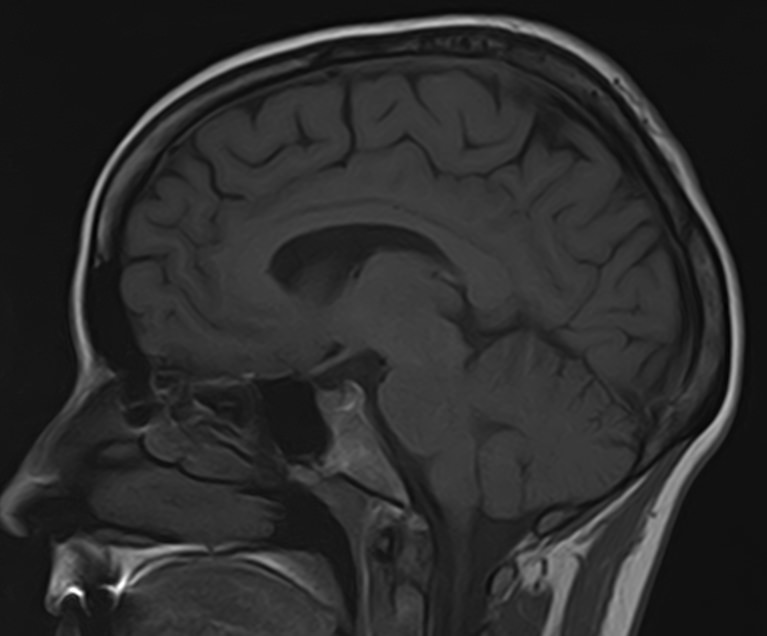

Золотым стандартом современной диагностики патологии головного мозга является магнитно-резонансная томография. Высокая информативность, отсутствие вредного рентгеновского излучения, достаточная быстрота и доступная цена исследования являются основными преимуществами данной методики.

Стандартная МРТ головного мозга дает важную информацию о состоянии и структуре мозговой ткани для выявления большого числа заболеваний, в том числе опухолевых образований, демиелинизирующих заболеваний, воспалительных процессов головного мозга и мозговых оболочек. Стандартную МРТ головного мозга дополняет МР-ангиография, которая отображает состояние артериальной системы кровоснабжения головного мозга. МР-венография головного мозга позволяет детально изучить особенности анатомического и функциональной состояния венозного русла головного мозга.